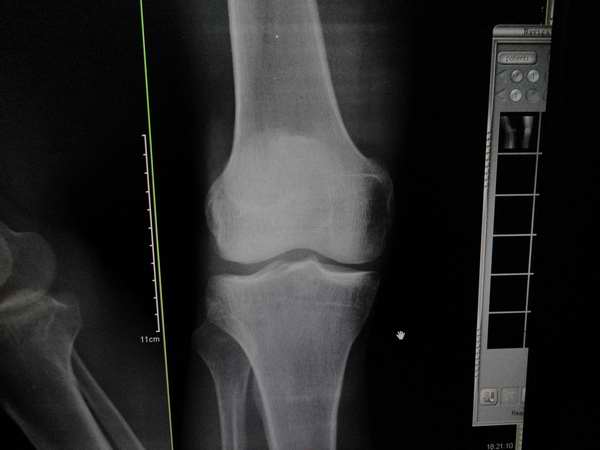

标题: X7107:看法,外伤,患者膝关节间隙内窄外宽改变,你们会不 [打印本页]

标题: X7107:看法,外伤,患者膝关节间隙内窄外宽改变,你们会不

1、外伤患者,可以提示半月板损伤,也可以写结合临床。

第一例:建议行mri检查。

提示“膝关节间隙内窄外宽改变,请结合临床或进一步检查”。看不见半月板,普放不能报。

第一个病例报告时要提示膝关节间隙馁窄外宽改变,建议结合临床或进一步检查,第二个病例支持考虑胫骨平台骨折后改变。

“膝关节间隙内窄外宽”如果没有外伤病史的话,也可以是膝关节退行性骨性关节病的表现,有没有半月板损伤平片没有权力诊断,有外伤史可以结合临床看外侧副韧带有没有损伤,拍双膝夹枕位片可有助于诊断